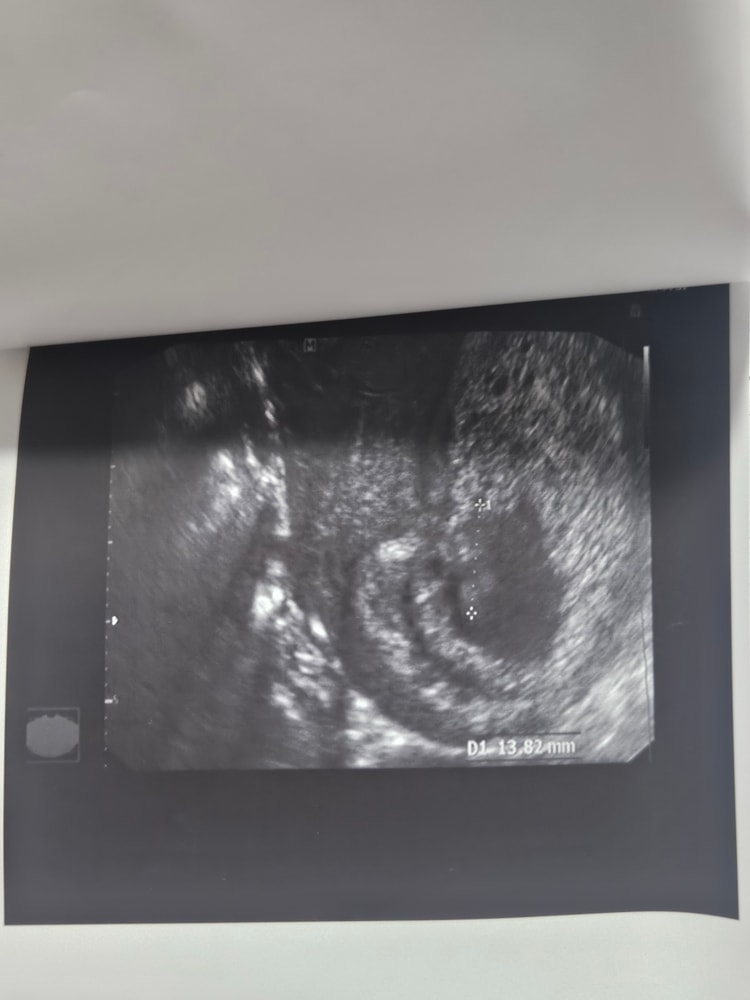

Беременность 9 недель. Сказали сделать контрольное УЗИ перед 1 скр. Сходила в платную клинику 11.04, эмбрион видно плохо( по словам УЗИ-специалиста рассасывается), СБ нет, поставили в заключении : "ЗБ 7.4 недель.Пузырный занос с множеством кист" . p.s: Ходила я на УЗИ 22.03 было СБ и эмбрион было видно. (За 2 недели-то меня что-то могло начать беспокоить).

12.04 я решила ещё в другую платную клинику сходить, эмбрион нашли с трудом(все так же не четко визуализируется), КТР 16мм, СБ +, прогрессирующая? ,тонус матки

прикреплю снимки узи за 12.04